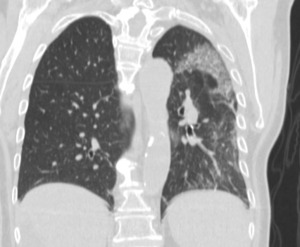

Of the total 47 cases, there were 16 (34.0%) case reports with only a CT, two (4.2%) with only a chest radiograph, and 26 (55.3%) with both a CT and a chest x-ray. Ground glass opacities were noted for 33 (69.8%) of patients with a CT (Figure 1). Among case reports with a CT published, crazy paving was noted by the radiologist in 10 (20.9%) of the case reports (Figure 2) and thickening of the interlobular septa was noted by the radiologist in 14 (30.2%) of the case reports.